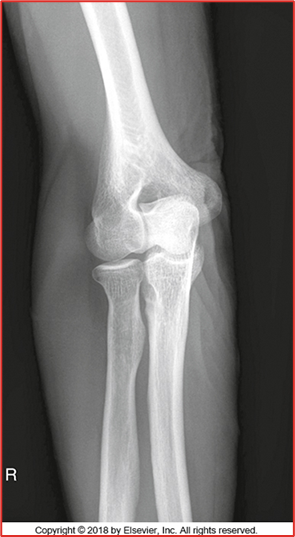

-All anatomy present

-Collimation is tight, want to open up some more

-Totally body positioning was not utilized because you cannot see the 3 concentric arches (trochlear notch, trochlear sulcus, ridges of the capitulum and trochlea)

-Not fully bent 90 degrees but close

-Coronoid process and radial head should be half superimposed (this image is a little more than half)

-Olecranon is in profile

-No marker

-REPEAT cause not in a true lateral position

Critique this lateral elbow image